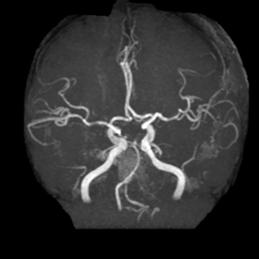

五、大脑中动脉开窗畸形

病例10:右侧大脑中动脉M1段开窗畸形

病例11:左侧大脑中动脉M1段开窗畸形

病例12:左侧大脑中动脉M1段开窗畸形